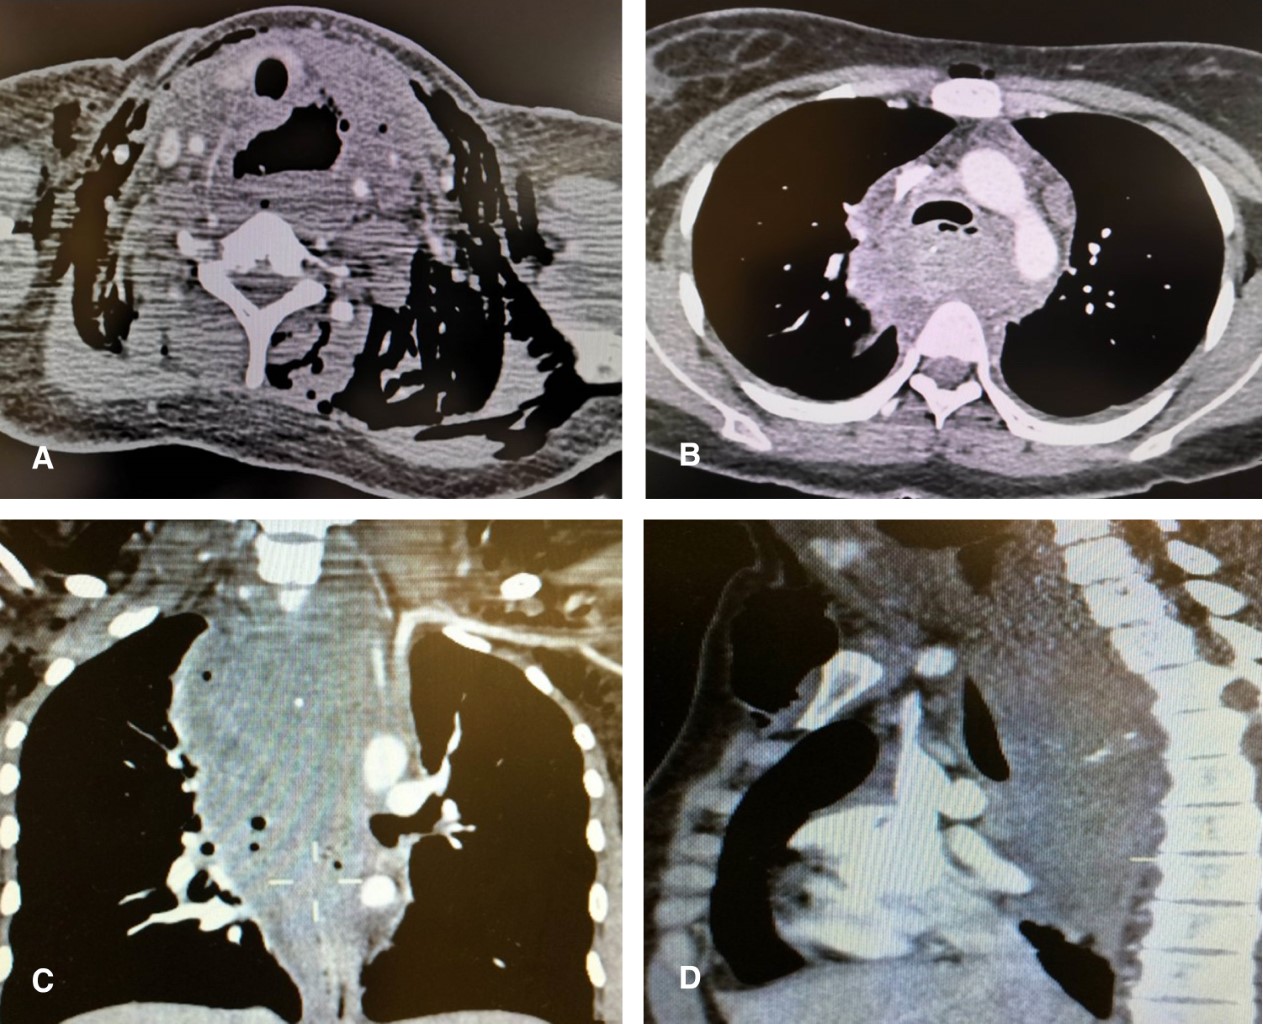

Se descartan antecedentes de ingestión o aspiración de cuerpo extraño, ingesta cáustica, y traumatismos, sin antecedentes de déficit neurológico ni trastornos de motilidad esofágica ni procesos otorrinolaringológicos inflamatorios o infecciosos previos. En la tomografía se corrobora perforación esofágica superior con disección enfisematosa cervical y torácica secundaria y presencia de un absceso mediastinal organizado con múltiples septos en su interior con volumen calculado de 600 mL de material purulento que excluye el lumen esofágico sin comprometer la vía aérea (Figura 2).

En las perforaciones cervicales el dolor puede estar acompañado de tumefacción e hipersensibilidad del músculo esternocleidomastoideo;15 un diagnóstico tardío de más de 24 horas posterior a la perforación está asociado a un incremento de la morbilidad y mortalidad.14,16 El diagnóstico temprano requiere un alto índice de sospecha, en el cual el enfisema es corroborado por la radiología simple y la evaluación tomográfica del cuello y tórax, como en nuestro reporte un trago de medio de contraste hidrosoluble confirma el diagnóstico y define el sitio exacto de la perforación.16,17 Aunque las complicaciones respiratorias e intratorácicas no son frecuentes en la perforación faringoesofágica (10% con respecto a las perforaciones esofágicas torácicas de 50%), el ensanchamiento mediastinal y el enfisema subcutáneo de la radiología simple de cuello y tórax permitieron identificar y diseñar el algoritmo terapéutico del absceso mediastinal detectado por la tomografía.17 Las anteriores consideraciones asociadas al sitio de perforación en la pared lateral de la hipofaringe podrían obedecer a un incremento súbito de la presión en la orofaringe e hipofaringe como resultado de una incoordinación neuromuscular y falla en el mecanismo de relajación del músculo cricofaríngeo, y explicar esta predisposición a la perforación faringoesofágica espontánea de nuestra paciente y de otros reportes previamente descritos.12,18-21

La presencia de un absceso mediastinal en el curso de una perforación esofágica debe denotar un diagnóstico tardío de la misma, la cual podría condicionar un drenaje incompleto de la cavidad septada a través del abordaje transesofágico endoscópico, como ocurrió inicialmente con nuestra paciente, y requerir un abordaje abierto transcervical para complementar el drenaje focalizado al mediastino superior y anterior que aseguró el desbridamiento mecánico y el drenaje exitoso de la cavidad mediastinal loculada. Estas condiciones facilitaron el cierre espontáneo de la perforación faringoesofágica y posteriormente, el cierre de la fístula faringomediastinal.